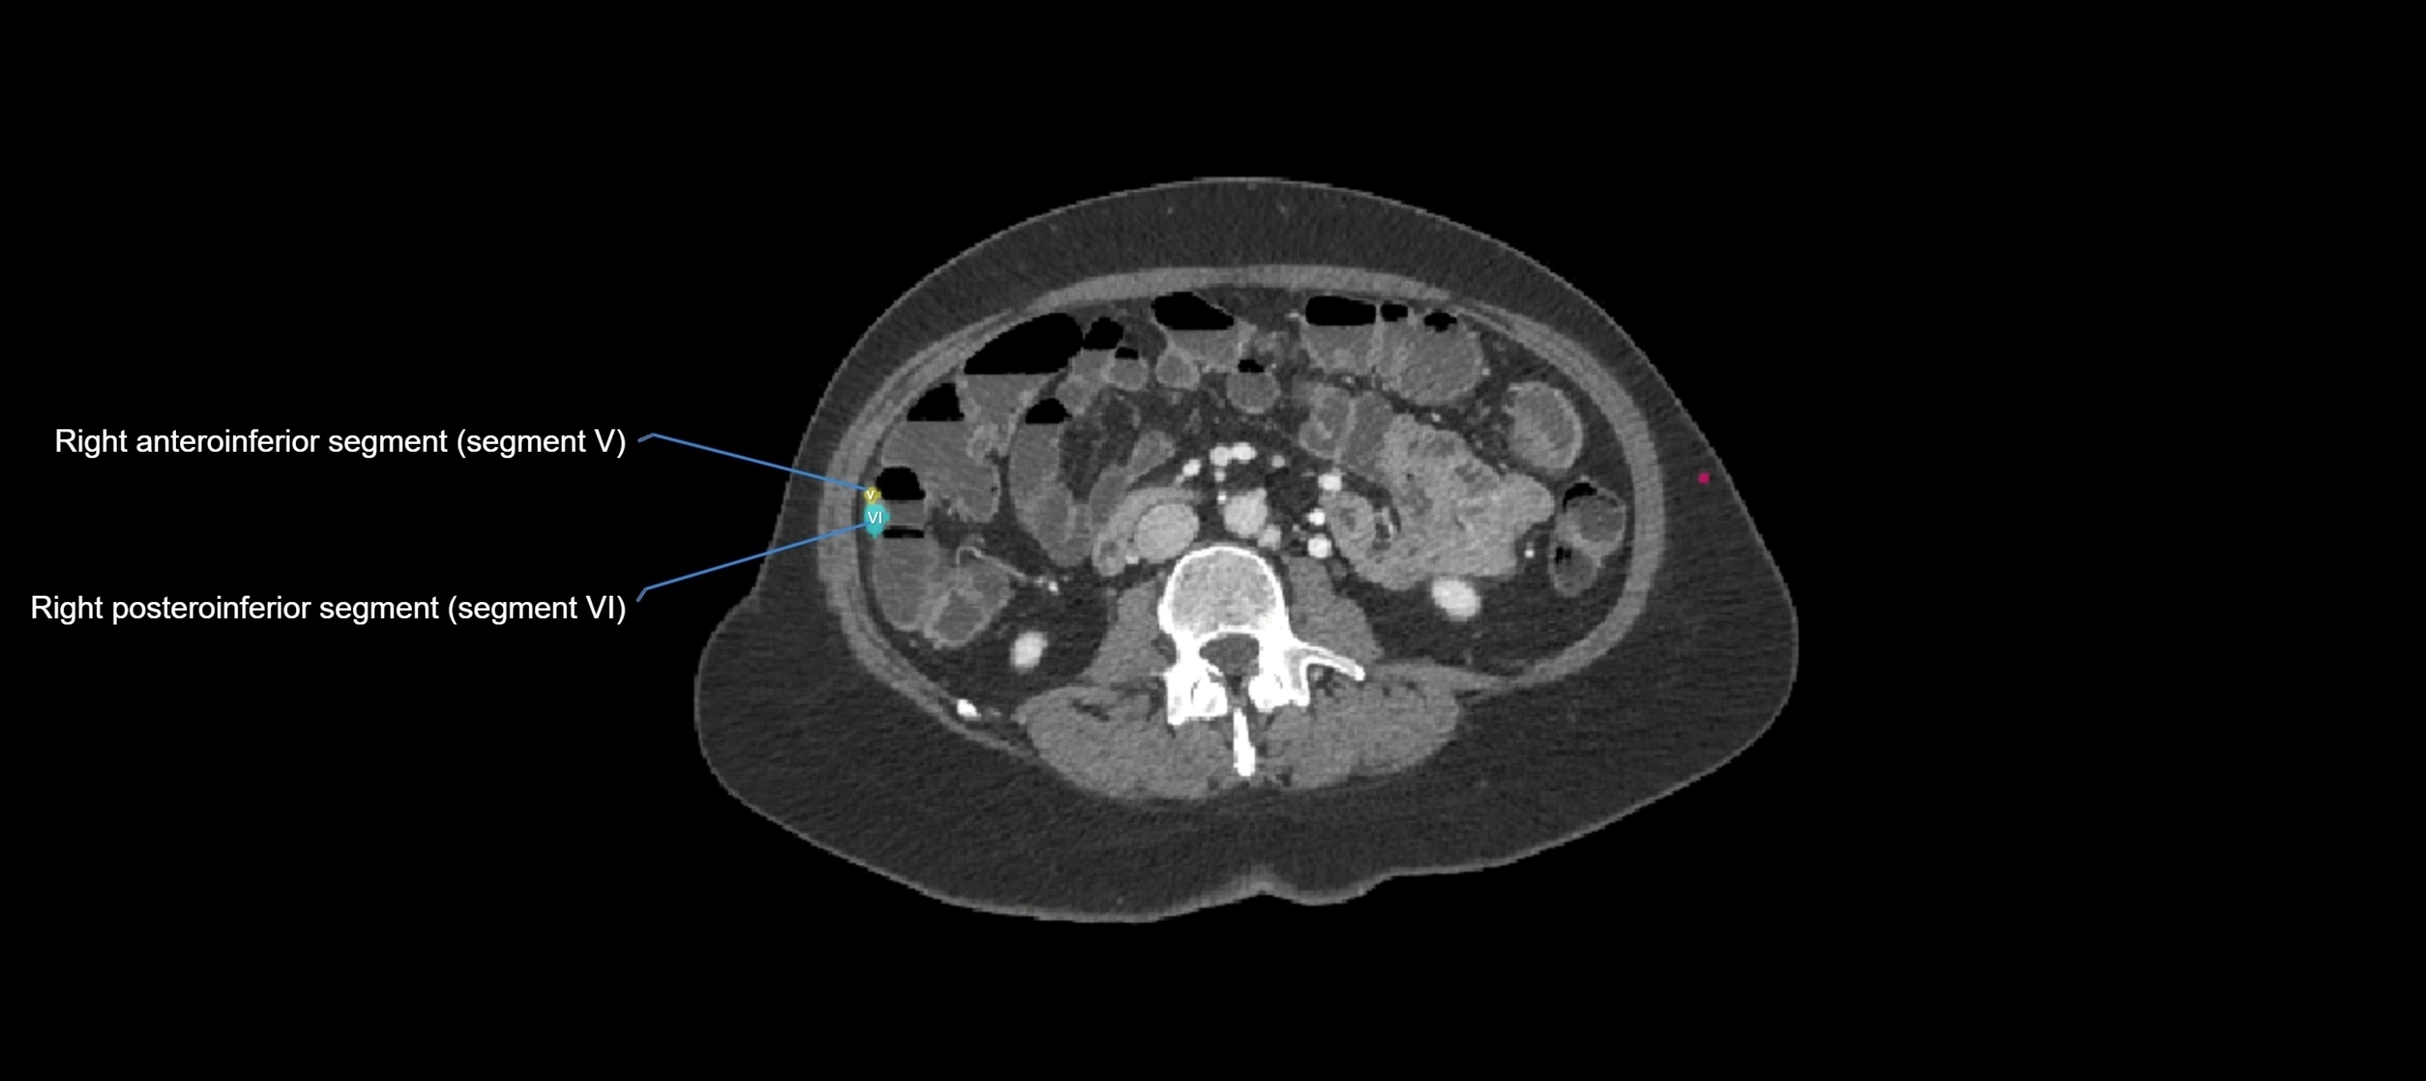

CT Appearance

CT Pre-Contrast:

• Caudate lobe appears as a soft-tissue density, isodense to the rest of the liver

• Enlargement may be appreciated in cirrhosis or Budd–Chiari syndrome

CT Post-Contrast:

• Homogeneous enhancement in the portal venous phase, similar to rest of liver

• Independent venous drainage into the IVC may be visualized

• Lesions follow characteristic CT enhancement patterns (HCC: arterial hyperenhancement with washout; hemangiomas: peripheral nodular enhancement with centripetal fill-in)

CT Venous Phase (functional significance):

• Caudate lobe often enhances relatively more than other lobes in Budd–Chiari syndrome, due to preserved venous outflow